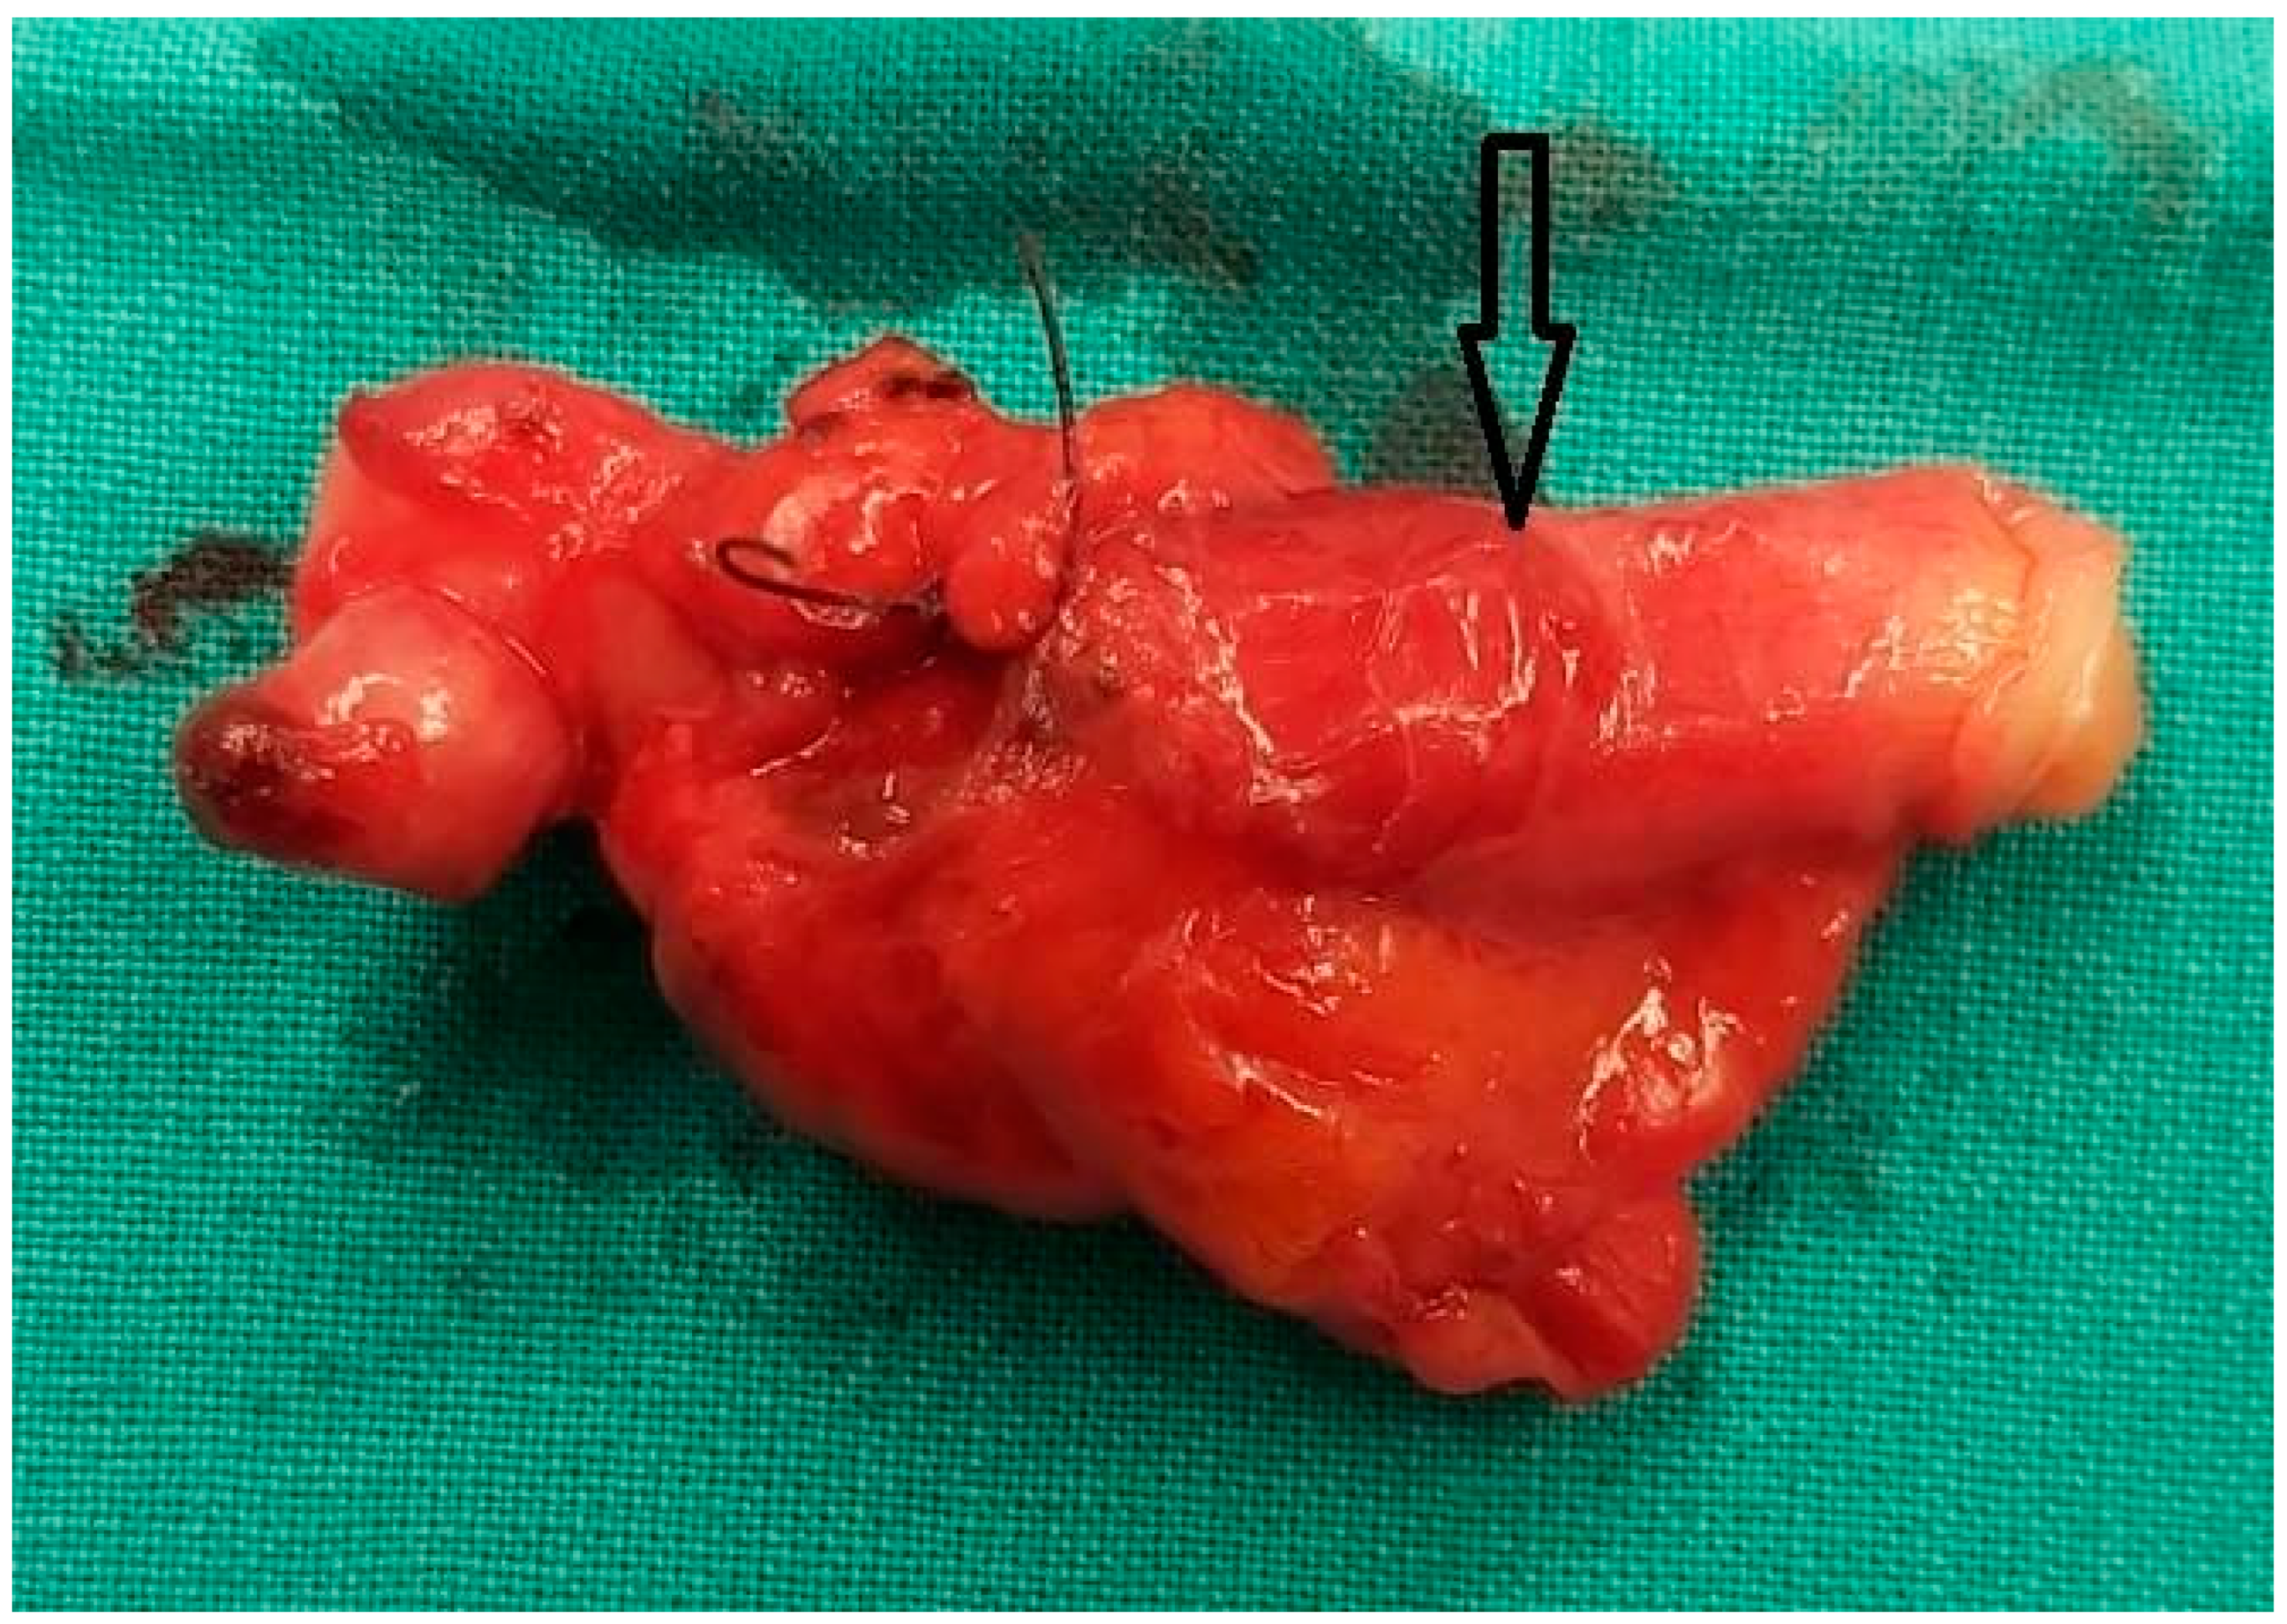

A Unique Case of Appendiceal Intussusception (Inversion): A Case in Bloom

Mantalovas, S.; Paschou, E.; Kountouri, I.; Sevva, C.; Papadopoulos, K.; Roulia, P.; Dagher, M.; Laskou, S.; Lagopoulos, V.; Koulouris, C.; et al. A Unique Case of Appendiceal Intussusception (Inversion): A Case in Bloom. Diagnostics 2024, 14, 555. https://doi.org/10.3390/diagnostics14050555